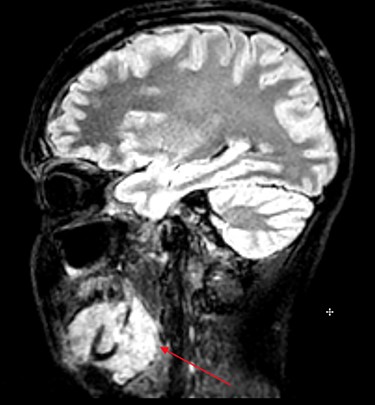

MRI head (sagittal view) showing Burkitt’s infiltrating the mandible and oral mucosa.

On the way to this scan, the patient experienced unilateral foot drop and was unable to walk. The scans revealed multifocal neoplastic deposits throughout the jaw, skull base, cervical spine and thyroid. These results, along with suspected malignant spinal cord compression (MSCC), prompted immediate admission to the head and neck ward at Royal Derby Hospital (RDH).